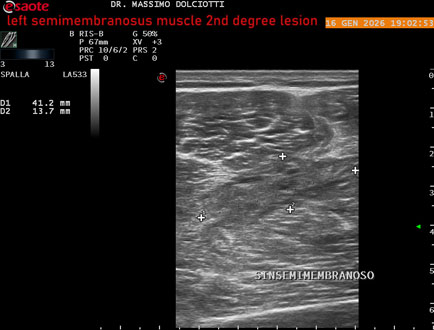

Data inserimento: 23/01/2026

Ecografia del: 16/01/2025

Strumento: Esaote MyLab Eight

Sonda: Lineare Multifrequenza 3-13 MHz

Età Paziente: M 23 anni

Motivazione dell'esame: dolore coscia sinistra da tre giornii.

Commento all'esame: le immagini ed il video documentano il muscolo semimembranoso sinistro disomogeneo per area iso-ipoecogena delle dimensioni di 38 x 14,7 mm per asse corto trasversale, 81 x 22 mm per asse longitudinale, come da lesione di 2° grado, con minimo versamento siero-ematico intramuscolare.

Conclusioni: lesione di 2° grado del muscolo semimembranoso sinistro (2nd degree lesion of the left semimembranosus muscle).